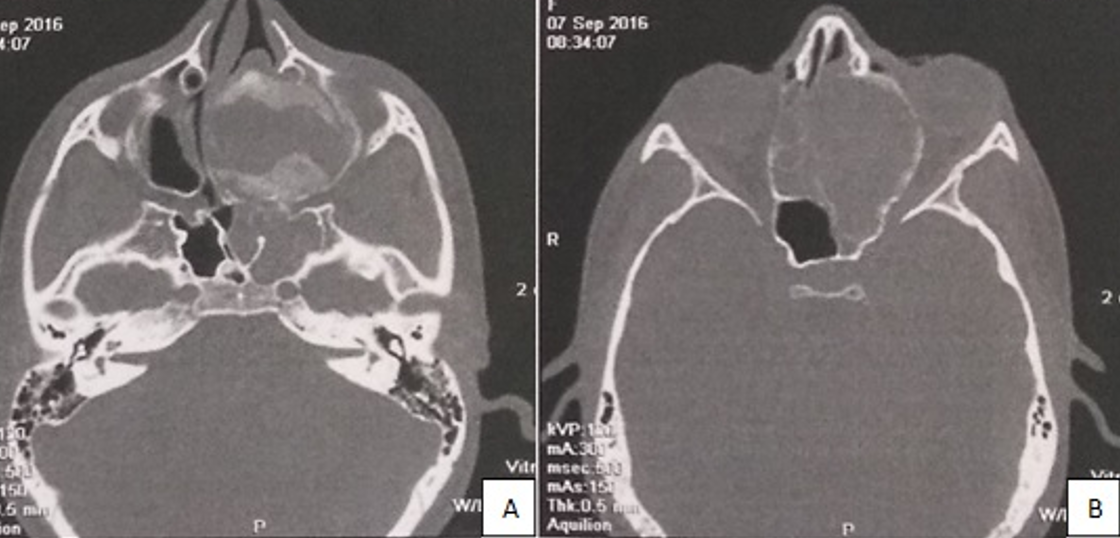

L'ostéoblastome est une tumeur osseuse bénigne rare, représentant 1% de toutes les tumeurs de l'os. Elle touche essentiellement les os longs, plus rarement les mâchoires. Les atteintes au niveau des mâchoires sont surtout retrouvées à la mandibule, l'atteinte naso-sinusienne est très rare. Le diamètre de la tumeur peut atteindre 10cm. A la radiographie, la tumeur peut avoir l'aspect d'une lésion radio claire bien ou mal définie, généralement parsemée de plaques de minéralisation. Le taux de récidive est très faible après exérèse chirurgicale et le risque de transformation maligne est très faible. Nous rapportons le cas d'une patiente âgée de 13 ans qui a consulté pour une obstruction nasale évoluant depuis 3 mois avec des épisodes d'épistaxis et un flou visuel gauche. L'examen a trouvé un volumineux cornet à muqueuse polypoïde comblant toute la fosse nasale gauche avec une exophtalmie gauche axile. Le scanner du massif facial a montré un processus expansif fronto-ethmoïdal gauche de 50 x 47 x 36mm, spontanément hypodense hétérogène non réhaussé après injection du produit de contraste (PDC), responsable d'une destruction du labyrinthe ethmoïdal, d'une souflure des parois osseuses avec effet de masse sur l'orbite homolatéral. Le diagnostic évoqué était une mucocèle fronto-ethmoïdale. D'où la décision d'opérer par voie endonasale. La section de la tête du cornet moyen a ramené du liquide épais blanchâtre rappelant une mucocèle infectée. Nous avons complété par une résection du cornet moyen. L'examen histologique a conclu à un ostéoblastome du cornet moyen. Les suites étaient marquées par une régression de l'exophtalmie sans récidive après un recul de 1 an.